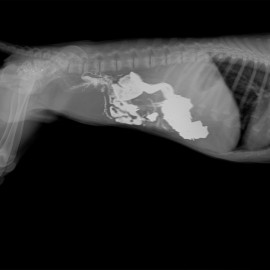

Обратились в ветеринарную клинику 13.07.2021г с жалобами на отсутствие аппетита, вялость, рвоту, потерю веса. Собаке были проведены осмотр, ОАК, БХАК, УЗИ брюшной полости, контрастная рентгенография желудочно-кишечного тракта.

Поставлен диагноз: Инородные предметы в желудке, кишечная непроходимость. Во время операции в полости желудка и кишке обнаружены свинцовые пластинки.